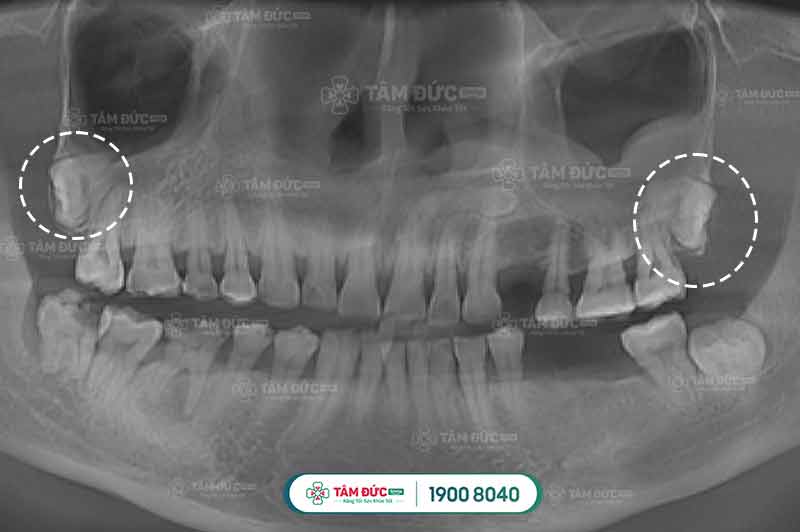

Đối với những chiếc răng khôn mọc lệch lạc, mọc ngầm này, dù răng Quý khách có bệnh lý như thế nào rặng hay nhẹ cũng sẽ được bác sĩ chỉ định nhổ bỏ ngay vì nó ảnh hưởng rất lớn đến sức khỏe người bệnh.

Trường hợp răng khôn mọc lệch, mọc ngầm